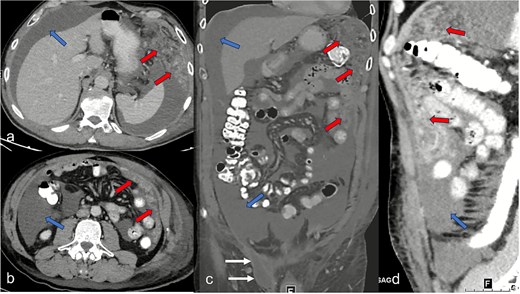

A 52-year-old male patient presented for surgical treatment of a recurrent hernia in the right groin. The preoperative sonography revealed a hernial orifice with a diameter of ~1 cm. In addition, there was clear ascites with a collection of fluid in the spermatic funiculus and a suspected mural tunica vaginalis. A subsequent magnetic resonance imaging (MRI) examination of the pelvis showed a similar picture (Fig. 1). Due to the suspicious appearance of the tunica vaginalis, the recurrent hernia was not repaired at that time. In the renewed physical examination and history taking, the patient reported not only the familiar painful feeling of pressure in the area of the known inguinal hernia but also an increasing feeling of fullness over the entire abdomen. He had also lost 3 kg in weight in the last two months. He had been professionally exposed to asbestos while working as a master electrician in old houses. In the blood count, the C-reactive protein was slightly elevated at 1.88 mg/dl, the thrombocytes at 456 000/μl and the leukocytes at 12 000/μl. The subsequent computed tomography (CT) thorax and abdomen revealed a peritoneal carcinomatosis with ascites without evidence of a primary tumor (Fig. 2). An ascites puncture with subsequent cytological analysis revealed no pathological findings. The subsequent diagnostic laparoscopy revealed a four-quadrant metastasis with nodular structures on the peritoneum (Fig. 3) and the greater omentum. Biopsies taken from the peritoneum and greater omentum revealed a malignant high-grade epithelioid mesothelioma of the peritoneum (Fig. 4). After the tumor conference decision, another laparoscopy was performed to reduce the tumor tissue, after which the affected greater omentum and part of the peritoneum were removed. Hyperthermic intraperitoneal chemotherapy (HIPEC) was then carried out, which was well tolerated and led to a complete remission during the 24-month follow-up period.

Hematoxylin and eosin staining with a 7.2-fold (a, overview image) and 40-fold (b, detail image) magnification. The histological images show a malignant epithelioid mesothelioma of the peritoneum; atypical tumor cell clusters located in papillary and exophytic formations can be seen.